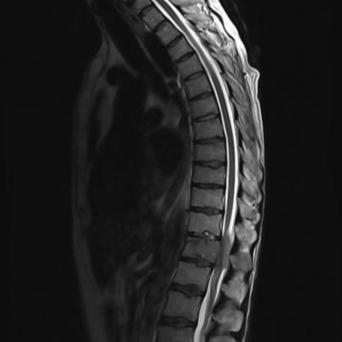

Microangiopathie thrombotique

La microangiopathie thrombotique (MAT) est une urgence médicale. Elle recouvre plusieurs pathologies aux mécanismes, tableaux cliniques et traitements distincts. Les progrès récents dans la compréhension de leur physiopathologie ont permis de mieux les identifier et les classifier, tandis que des thérapeutiques spécifiques en ont grandement amélioré le pronostic. Une identification précoce est donc cruciale.